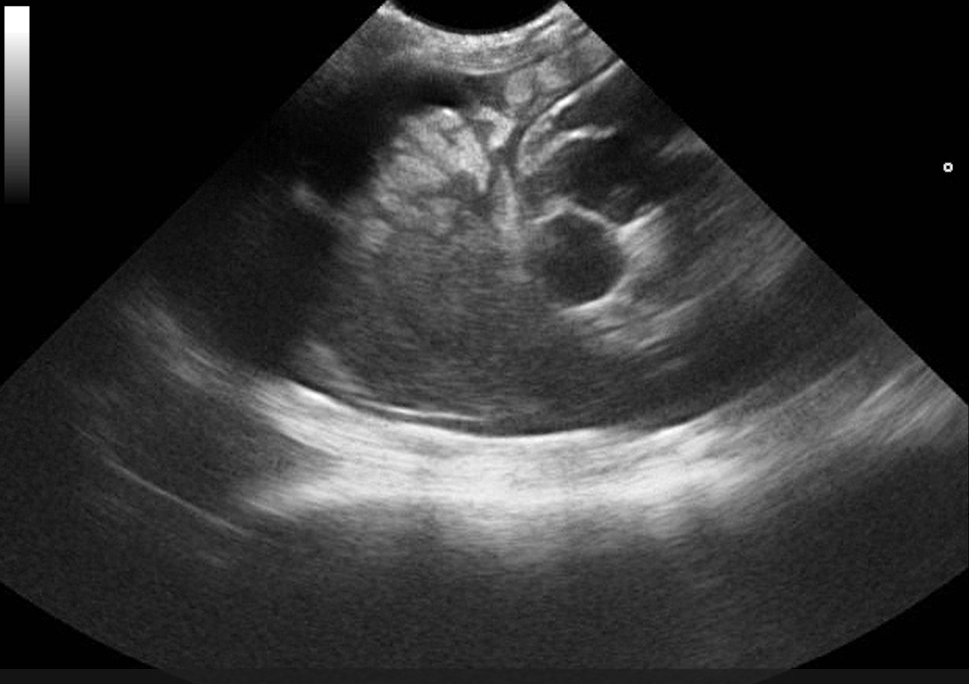

Játra, žlučník

Praktická sonografie jater a žlučových cest se zaměřením na klinicky významné nálezy.

Jak správně měřit játra, rozlišit strukturální změny a interpretovat nález v diferenciální diagnostice ikterického pacienta.